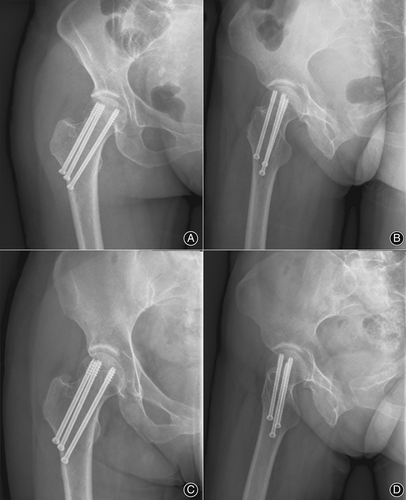

三枚空心螺钉分别置于股骨颈的前上、后上和下中部,并进一步穿过骨折线,距离软骨下骨小于5毫米。下方螺钉会适当压紧,另两枚螺钉则作为定位螺钉而不施加压力。

在术后随访中,所有患者均在24小时内通过X光和CT扫描进行评估。两名外科医生在术后24小时、6个月及2年内评估股骨颈骨折的复位质量,包括颈干角、后倾角以及股骨颈缩短量。出院后,要求患者定期前往门诊进行影像检查和功能评估(Harris髋关节评分,HHS)。此外,通过X光片和症状识别并发症,如固定失败、不愈合及股骨头坏死,直至最终随访。

在经皮复位组中,测量并分析了股骨颈骨折复位质量的放射学参数。术前病例和术后即刻病例的椎弓根角、后倾角和FNS数量存在显著差异(p<0.05)。然而,不同时间点(术后24小时、6个月和2年内)的术后病例测量值没有统计学差异(p>0.05)。

所有患者术后2年内均实现骨愈合,无骨不连。在经皮复位组中,一名患者在术后2年发生AVN,其他患者在最后一次随访时没有AVN。一名患者因螺钉退回而发生固定失败,但最终实现了骨愈合。在原位固定组中,两名患者在最后一次随访时出现AVN。因此,3名AVN患者被排除在功能结果分析之外,45名患者被纳入功能分析。在通过kappa分析评估髋关节功能结果时,一致性系数达到0.814。实践证明,评价结果具有较高的可信度。经皮组术后6、12和24个月的平均HHS均优于原位固定组。